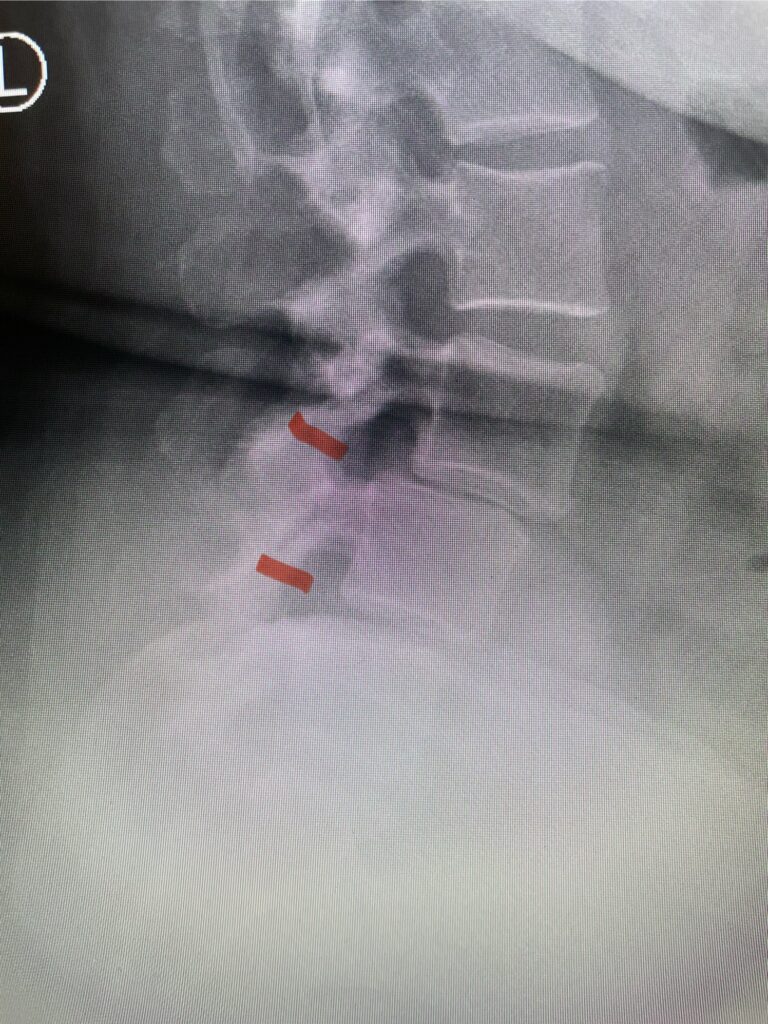

Patients may require an occipital-cervical fusion for both cranio-cervical and atlanto-axial instability, depending on the anatomy. Patients who have long segment posterior cervical fusions can sometimes […]